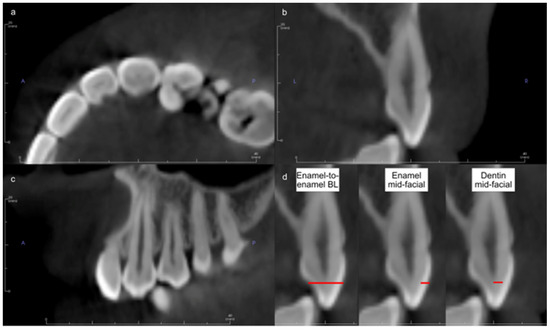

Automated Measurements of Tooth Size and Arch Widths on Cone-Beam Computerized Tomography and Scan Images of Plaster Dental Models

by Thong Phi Nguyen, Jang-Hoon Ahn, Hyun-Kyo Lim, Ami Kim and Jonghun Yoon

Measurements of tooth size for estimating inter-arch tooth size discrepancies and inter-tooth distances, essential for orthodontic diagnosis and treatment, are primarily done using traditional methods involving plaster models and calipers. These methods are time-consuming and labor-intensive, requiring multiple steps. With advances in cone-beam [...] Read more.

Measurements of tooth size for estimating inter-arch tooth size discrepancies and inter-tooth distances, essential for orthodontic diagnosis and treatment, are primarily done using traditional methods involving plaster models and calipers. These methods are time-consuming and labor-intensive, requiring multiple steps. With advances in cone-beam computerized tomography (CBCT) and intraoral scanning technology, these processes can now be automated through computer analyses. This study proposes a multi-step computational method for measuring mesiodistal tooth widths and inter-tooth distances, applicable to both CBCT and scan images of plaster models. The first step involves 3D segmentation of the upper and lower teeth using CBCT, combining results from sagittal and panoramic views. For intraoral scans, teeth are segmented from the gums. The second step identifies the teeth based on an adaptively estimated jaw midline using maximum intensity projection. The third step uses a decentralized convolutional neural network to calculate key points representing the parameters. The proposed method was validated against manual measurements by orthodontists using plaster models, achieving an intraclass correlation coefficient of 0.967 and a mean absolute error of less than 1 mm for all tooth types. An analysis of variance test confirmed the statistical consistency between the method’s measurements and those of human experts. Full article